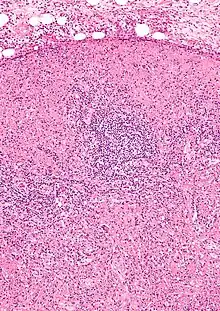

| Micrograph of a lymph node with Kikuchi disease showing the characteristic features (abundant histiocytes, necrosis without neutrophils). H&E stain. | |